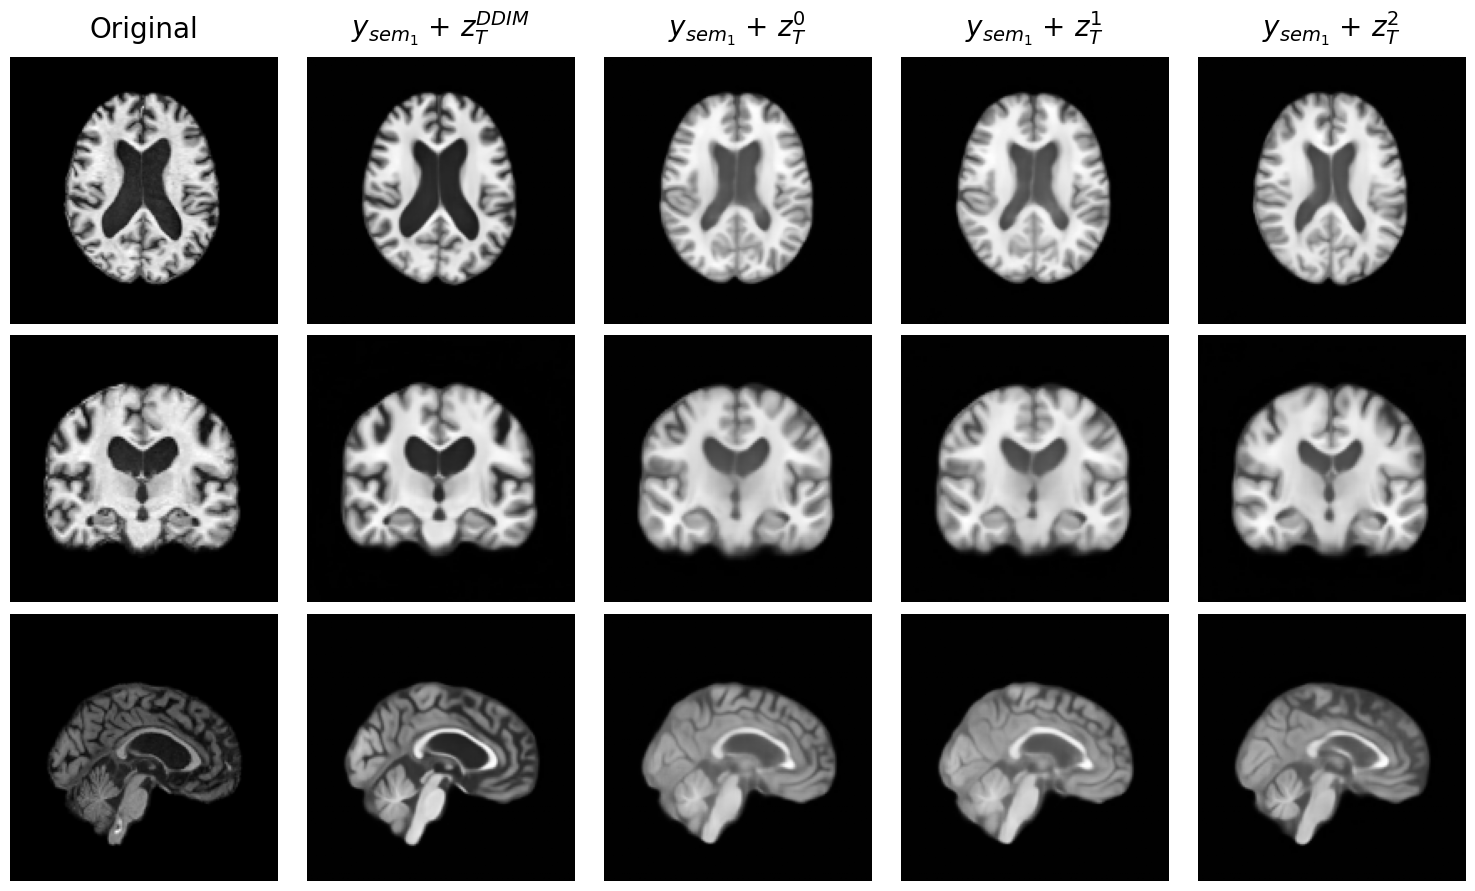

5.3 Semantic Guidance Enables Reconstruction from Pure Noise

To assess the semantic richness of the learned representation, we perform reconstructions using only the semantic code and a randomly sampled stochastic code . This setup evaluates whether the semantic code alone can guide the reverse diffusion process to generate anatomically plausible MR that contains structure information of .

Figure 4 shows qualitative reconstructions for two randomly selected subjects: a CN individual (left) and an AD patient (right). For both cases, reconstructions are generated by fixing the semantic code and sampling multiple stochastic codes . Across samples, the reconstructions preserve global brain morphology, indicating that the semantic code captures the high-level anatomical and pathological attributes of the subject, while the stochastic component contributes only to low-level variability.

In the CN subject, cortical thickness and brain volume are preserved across stochastic samples. In contrast, the AD subject reconstructions consistently display expected atrophic patterns, such as enlarged ventricles and reduced hippocampal volume, despite variation in image details. These observations suggest that encodes disease-relevant structural information.

This behavior is consistent with prior findings in DAE Preechakul et al. (2022), where the semantic representation governs identity and structure, and the stochastic latent controls fine-grained appearance.